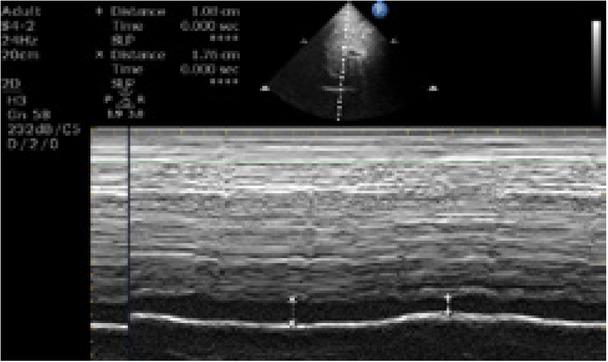

Volunteers who had given their consent were included in the study. After basic measurements, IVC and MAPSE measurements were performed with a phased array transducer (Mindray DC-60 Exp Ultrasound system, China) at 3.5–5 MHz in the B-mode scan. After the volunteer had rested for a while, IVC measurements were performed on the subxiphoid region, while the volunteer was in the supine position. By imaging the adjacency of the liver and heart through the subxiphoid window, the junction of the inferior vena cava and the left atrium was detected. A measurement was performed on the image obtained in the M-mode, approximately 2 cm distal from this part. Measurements were done, and the diameters of the vena cava in inspiration and expiration were recorded. A video recording was performed in the B-mode during at least three breathing cycles. Maximum IVC measurement was performed from one inner wall to the other inner wall during inspiratory and expiratory phases in the B-mode, where the edges of the IVC were clearly visible (Fig. 1). While the patient is in the supine position, to evaluate mitral annular plane systolic motion, which provides important information about the patient’s left ventricular functions, an M-mode tracing was obtained from the junction where the mitral annulus combines with the lateral free wall in the apical four-chamber view. In this tracing, two movements towards the apex were observed. The first forward movement was the systolic movement of the annulus, while the second positive wave was low amplitude and belonged to the atrium systole. Taking presystolic thinning as the baseline level in these two movements, the distance from baseline to peak gave information about the magnitude of systolic movement for systolic function (Fig. 2). Both the IVC and MAPSE measurements were repeated three times, and an average was calculated for the analysis. After the initial US measurements were completed, the volunteers were allowed to proceed to the blood donation procedures. Each procedure took 10–15 minutes. Following the IVC and MAPSE measurements and 450 mL blood donation, and after 10 minutes of rest, the initial measurement procedures were repeated without changing the body position of the volunteer, and vital signs measurements were recorded in the same way.

Fig. 1

Ultrasound image of IVC diameter during inspiration and expiration